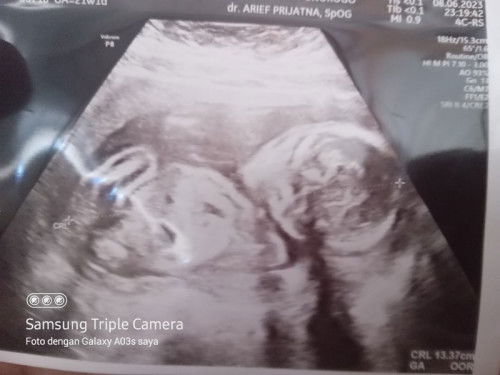

Bun udah ada yang usg 20 minggu ke atas? Itu udah di ukur apanya aja ? Soalnya kmren ak usg cuma di ukur panjang janin aja sma djj yrus itu di keterangannya Ga oor gtu kan aneh klo gk kedekteksi umurnya 🥺🥺🥺 doalnya saya ada kelugan hipertensi dan gula bun,, takutnya nutrisinya gk sampek ap gmn gtu mlah gk di jelas i sma sekali #seriusnanya #bantusharing #ingintahu